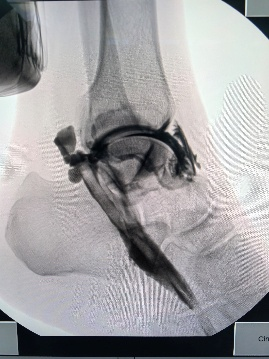

为进一步明确诊断,为患者实施了“踝关节腔造影+动态透视”检查。在造影剂注入踝关节腔后,动态影像清晰显示:显影液沿踇长屈肌腱鞘自踝关节向足趾囊肿方向持续流动,准确锁定了关节囊与囊肿之间的异常交通通道。该检查不仅明确了“踝源性”的诊断,也为手术方案设计提供了精准的定位依据。

术前踝关节造影